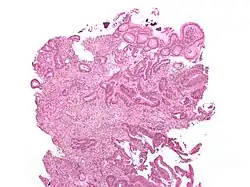

O tipo do tumor é geralmente diagnosticado através da análise de tecido removido através de uma biópsia ou cirurgia. O diagnóstico patológico geralmente contém a descrição histológica do cancro, e o grau. O tipo mais comum de cancro colorretal é adenocarcinoma, que compõe 95% dos casos - acredita-se que a maioria dos casos de cancro colorretal envolvam tumores originários de pólipos adematosos. Outros tipos, mais raros, de cancro colorretal, incluem linfoma e carcinoma espinocelular. As causas do cancro colorretal não são conhecidas com exatidão no presente.

Adenocarcinoma é um tipo de tumor maligno epitelial, que se origina do epitélio glandular da mucosa colorretal. Tal tumor invade a parede, infiltrando a mucosa muscular, a submucosa, e daí, a muscularis propria. As células do tumor abrigam estruturas tubulares irregulares, de estrutura pluristratificada, lúmens múltiplos, e estromas reduzidos. Por vezes, as células do tumor secretam muco, que invade o fluido intersticial, produzindo grandes agrupamentos de muco e colóide (que, visualmente, aparecem como "espaços vazios") - é o chamado adenocarcinoma colóide, pouco diferenciado. Se o muco permanece dentro da célula do tumor, o muco empurra o núcleo celular para a periferia da célula - célula do tipo signet-ring. Dependendo da arquitetura glaudular, pleomorfismo celular, e padrão da secreção de muco, o adenocarcinoma pode ser categorizado em três graus de diferenciação: bem diferenciado, moderadamente diferenciado, e mal diferenciado.[48]